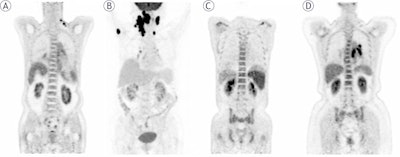

The initial PET maximum-intensity projection images, and lymph nodes pathology confirmed DLBCL with normal (A), focal increased in the right humerus (B), diffuse increased (C, D).The initial PET maximum-intensity projection images, and lymph nodes pathology confirmed DLBCL with normal (A), focal increased in the right humerus (B), diffuse increased (C, D).Radiation and Oncology